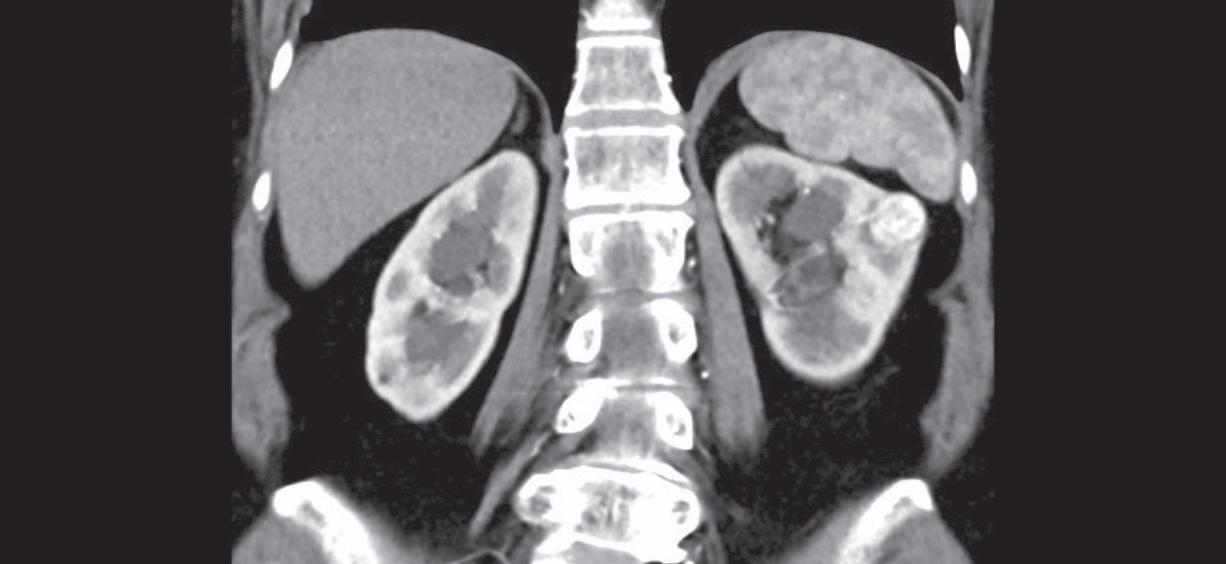

Obr. 2. Nález na počítačové tomografii u pacienta s parastomální hernií po otevřené radikální cystektomii s použitím ileálního konduitu.

Fig. 2. Computed tomography finding in a patient with parastomal hernia following open radical cystectomy with ileal conduit.